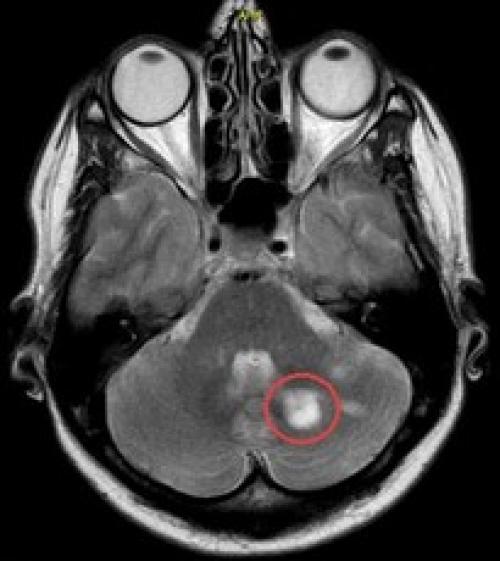

![]() | ![]() | ![]() |

| Выход пломбировочного материала за верхушку зуба вызывал жестокие боли во второй ветви тройничного нерва у мужчины. Вид сбоку:

зуба, кружком обведен | Стреляющая боль во всех трех ветвях была следствием плохого кровообращения в мозговых отделах тройничного нерва у пожилой женщины. Кружком обведен участок мозга, пострадавший от закупорки одного из сосудов головного мозга. Проверить сосуды головы и шеи | Невралгия тройничного нерва была у молодой женщины из-за давления одной из мозговых артерий на корешок тройничного нерва. На МР-томограмме видно пересечение тройничного нерва (идет вертикально) с артерией (идет горизонтально). Артерия оказывала давление на тройничный нерв в месте его выхода из ствола мозга. |